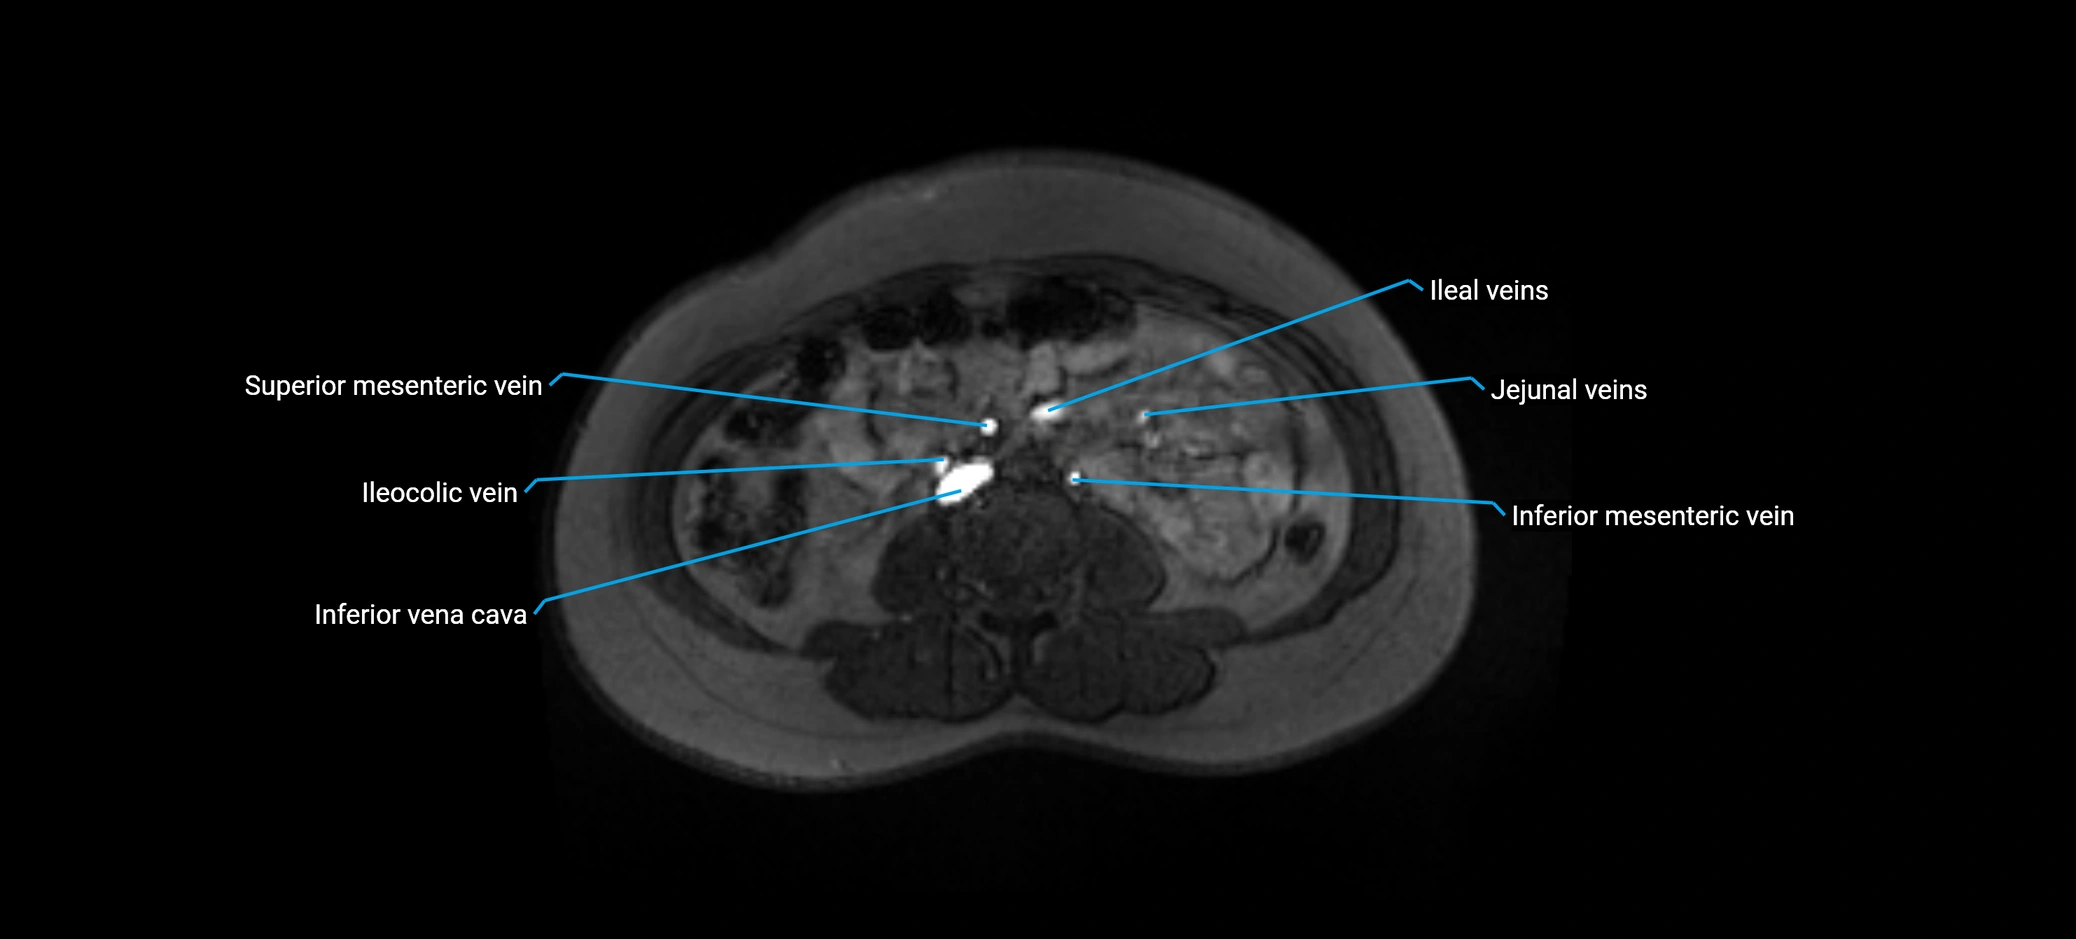

MRI image

image